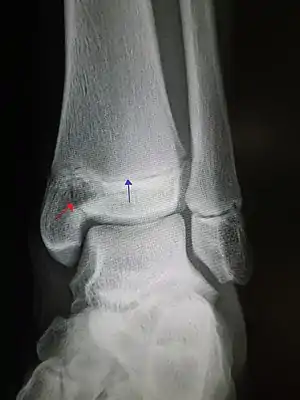

| An X-ray of the left ankle showing a Salter–Harris type III fracture of medial malleolus. Red arrow demonstrates fracture line while the blue arrow marks the growth plate. | |